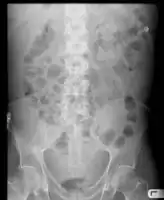

Ascites is the abnormal buildup of fluid in the abdomen.[1] Technically, it is more than 25 ml of fluid in the peritoneal cavity.[4] Symptoms may include increased abdominal size, increased weight, abdominal discomfort, and shortness of breath.[3] Complications can include spontaneous bacterial peritonitis.[3]

In the developed world, the most common cause is liver cirrhosis.[4] Other causes include cancer, heart failure, tuberculosis, pancreatitis, and blockage of the hepatic vein.[4] In cirrhosis, the underlying mechanism involves high blood pressure in the portal system and dysfunction of blood vessels.[4] Diagnosis is typically based on an examination together with ultrasound or a CT scan.[3] Testing the fluid can help in determining the underlying cause.[3]

Mild ascites is hard to notice, but severe ascites leads to abdominal distension. People with ascites generally will complain of progressive abdominal heaviness and pressure as well as shortness of breath due to mechanical impingement on the diaphragm.

Ascites is detected with physical examination of the abdomen by visible bulging of the flanks in the reclining person ("flank bulging"), "shifting dullness" (difference in percussion note in the flanks that shifts when the person is turned on the side), or in massive ascites, with a "fluid thrill" or "fluid wave" (tapping or pushing on one side will generate a wave-like effect through the fluid that can be felt in the opposite side of the abdomen).